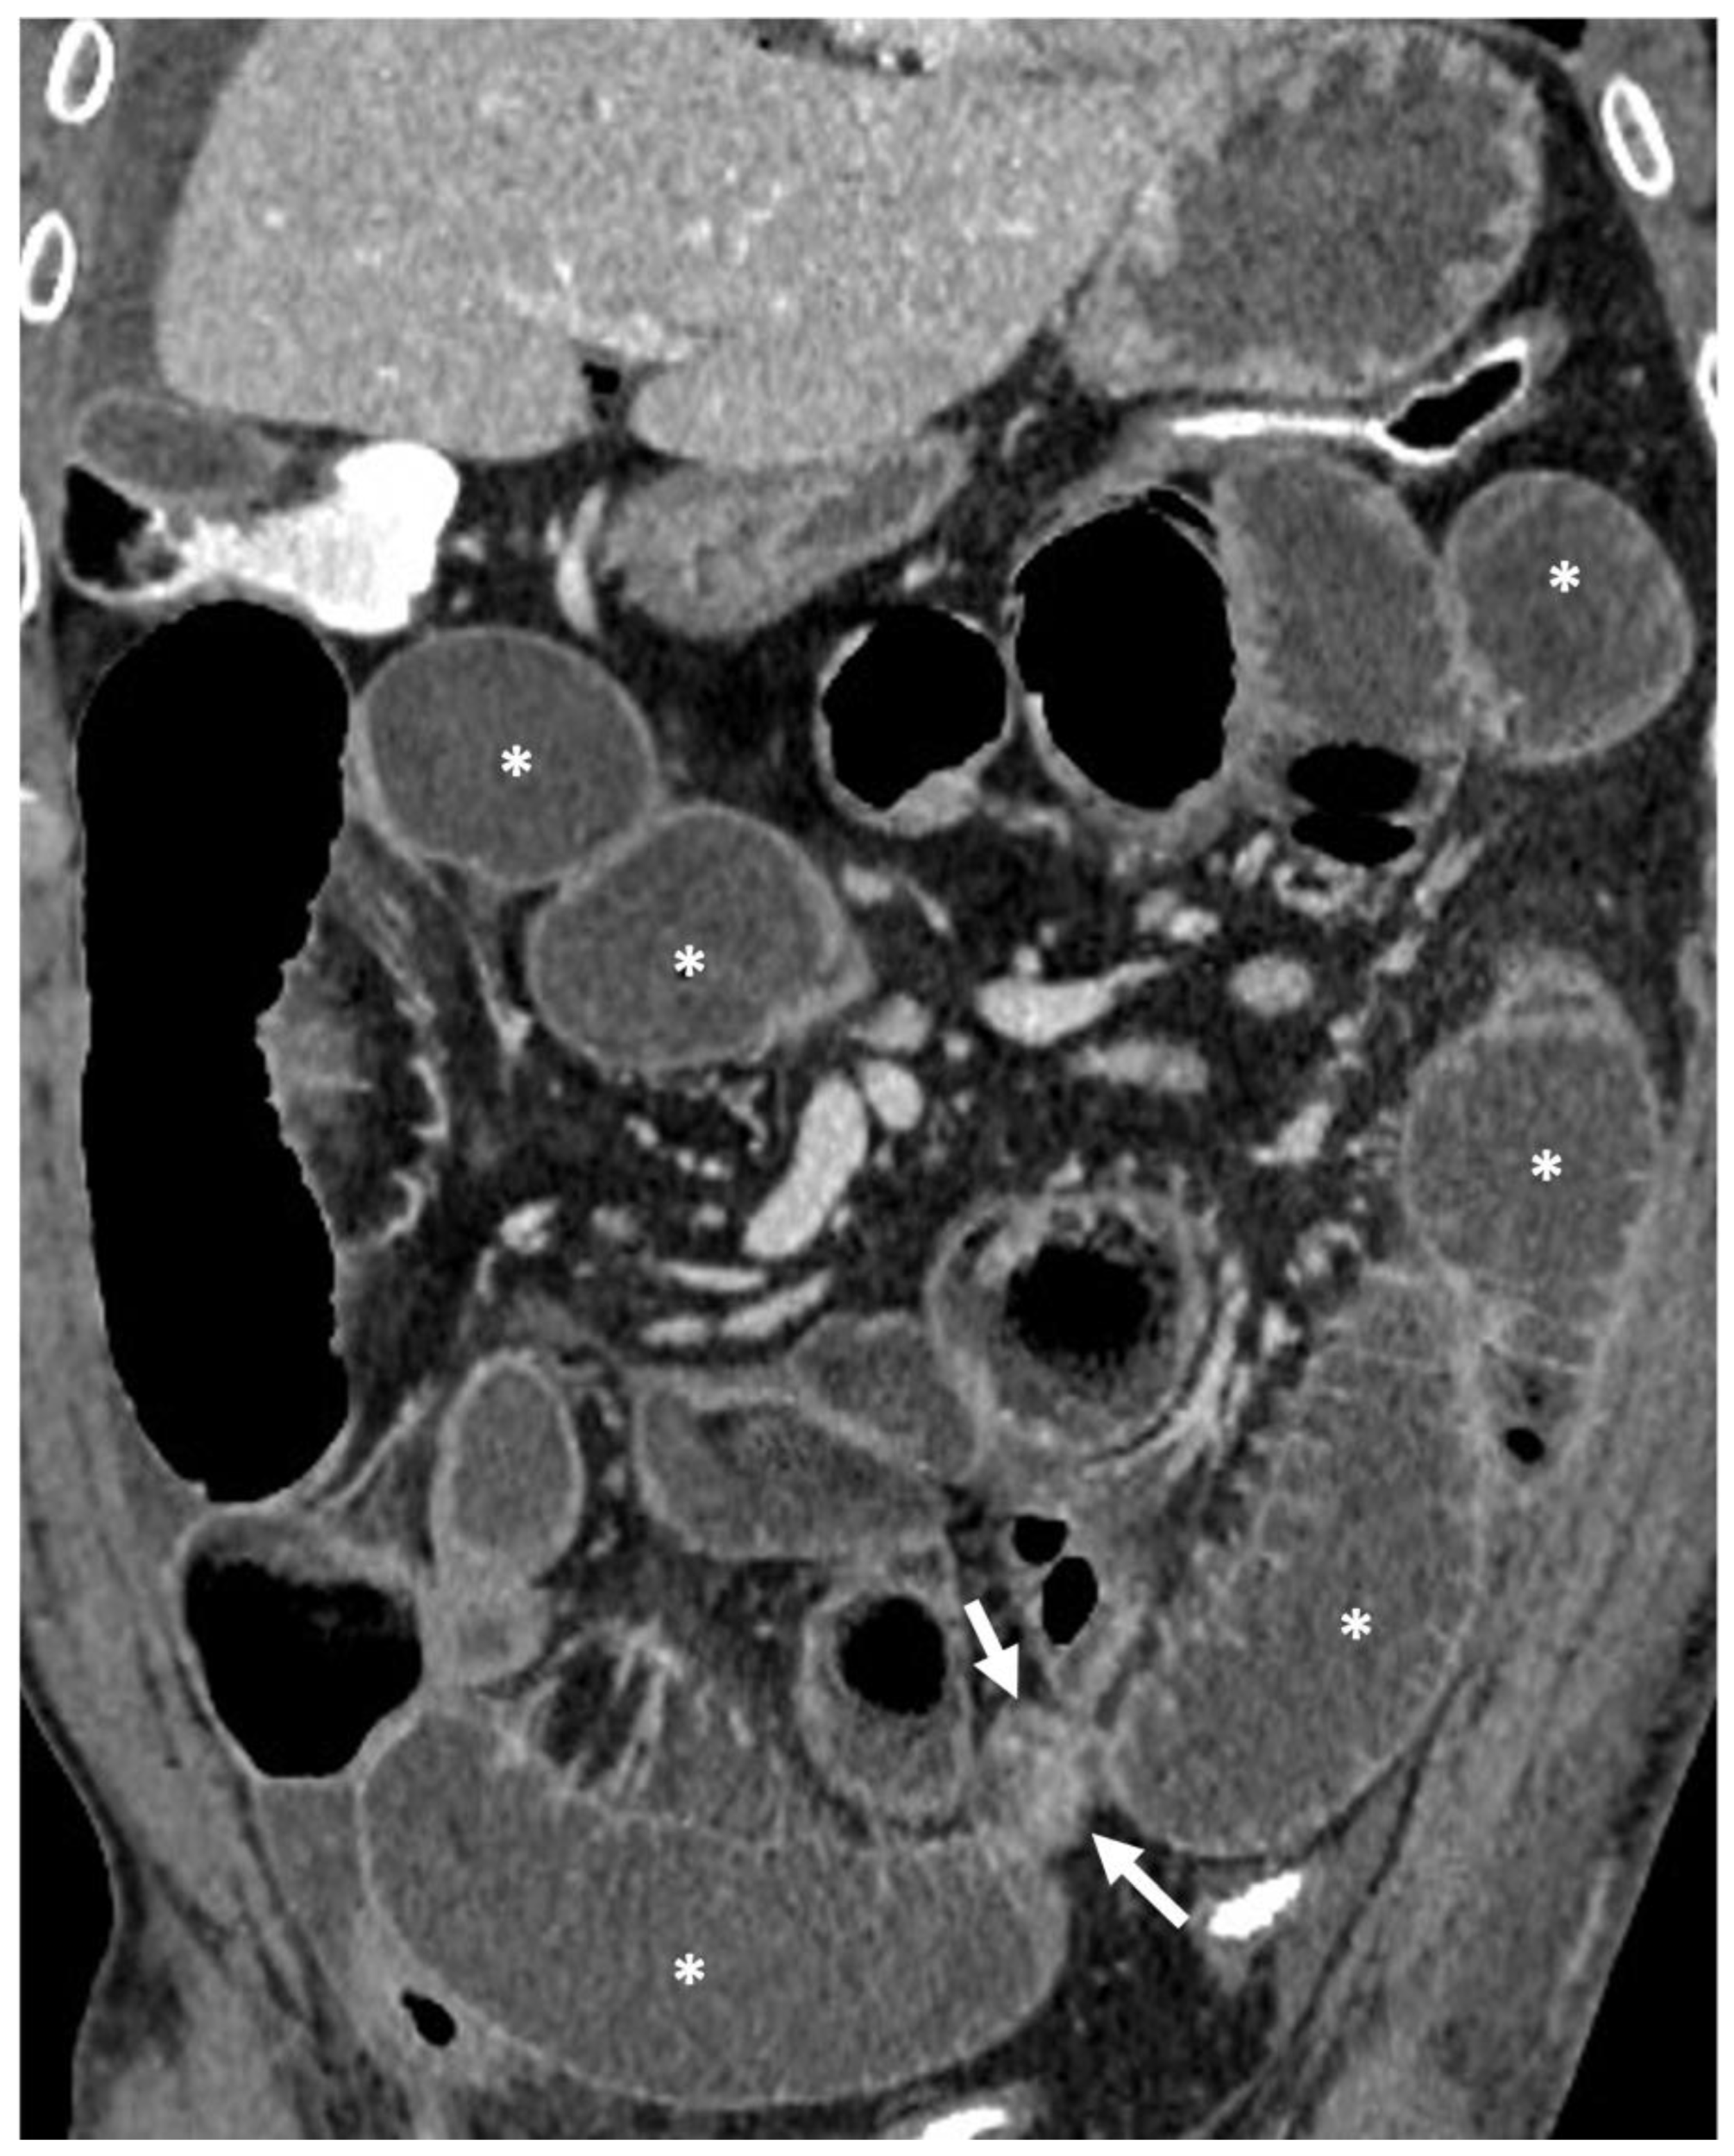

- Regarding the length of the bowel tract affected, a stricture is considered focal if it is less than 5 cm long, segmental if it is between 6 and 40 cm, and diffuse if it is longer than 40 cm [20,21,22]. In the case of multiple stenotic tracts, the healthy tracts interposed between the stenotic ones must not be considered.

- A normal bowel loop caliber ranges between 2 and 2.5 cm. A bowel lumen is dilated when it has a maximum diameter greater than 2.5–3 cm. The dilation is mild when the upstream lumen is dilated up to 4 cm and severe when it is more than 4 cm (Figure 3) [24]. Pre-stenotic bowel dilatation should always be checked, as it is a sign related to bowel obstruction. Moderate to severe stenosis was determined via double-contrast imaging (conventional barium study) with a sufficient amount of injected air, and stenosis was defined as stenosis in which the lumen was less than one half that of neighboring healthy intestine [25].